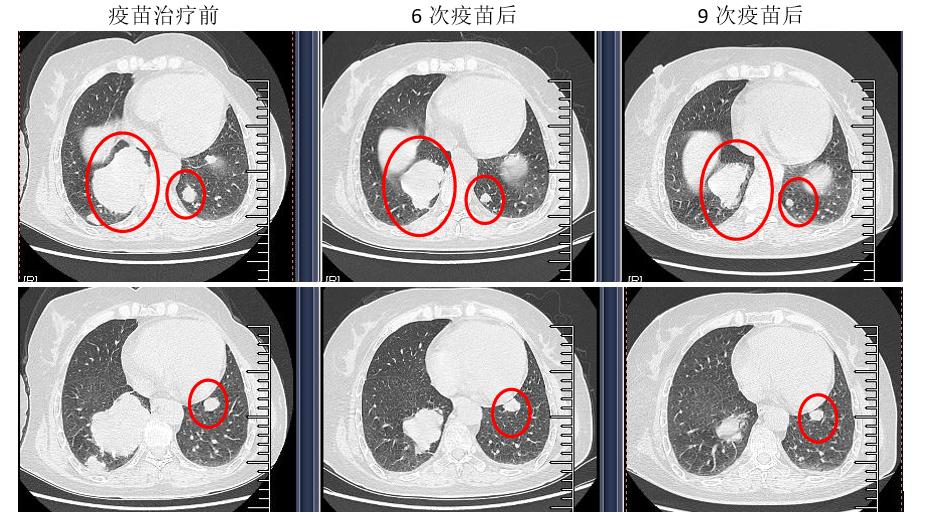

2020-02-05治疗中期,肺部多个病灶缩小明显,腹壁、右侧肾脏病灶、右侧髂骨病灶及额顶头皮包块较前稳定。

2020-04-21个体化新抗原肽纳米疫苗联合抗PD-1抗体的免疫综合治疗结束,肺部多个病灶仍持续缩小,腹壁包块、头皮包块稳定,右侧肾脏病灶及右侧髂骨病灶较前有所进展。